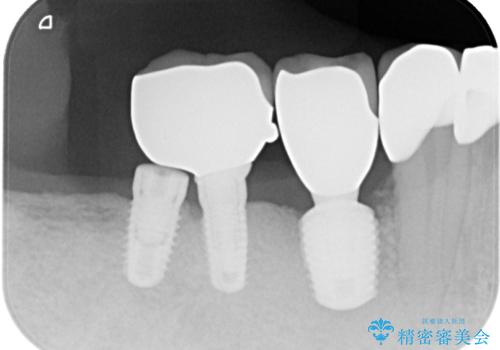

- 奥歯が割れてしまい、抜歯が必要となった患者様です。

以前にも歯が割れてインプラント治療を行いましたが、抜歯してからインプラント埋入→仮歯装着までに半年以上を要し、その間に残された歯への負担が大きくなり、左右反対側のセラミッククラウンが破折したことがありました。

そのため、当院に新しく導入した手法により、抜歯をした日にインプラントを埋入し、そのままを仮歯を装着することで、他の歯への負担を軽減する計画を立てました。